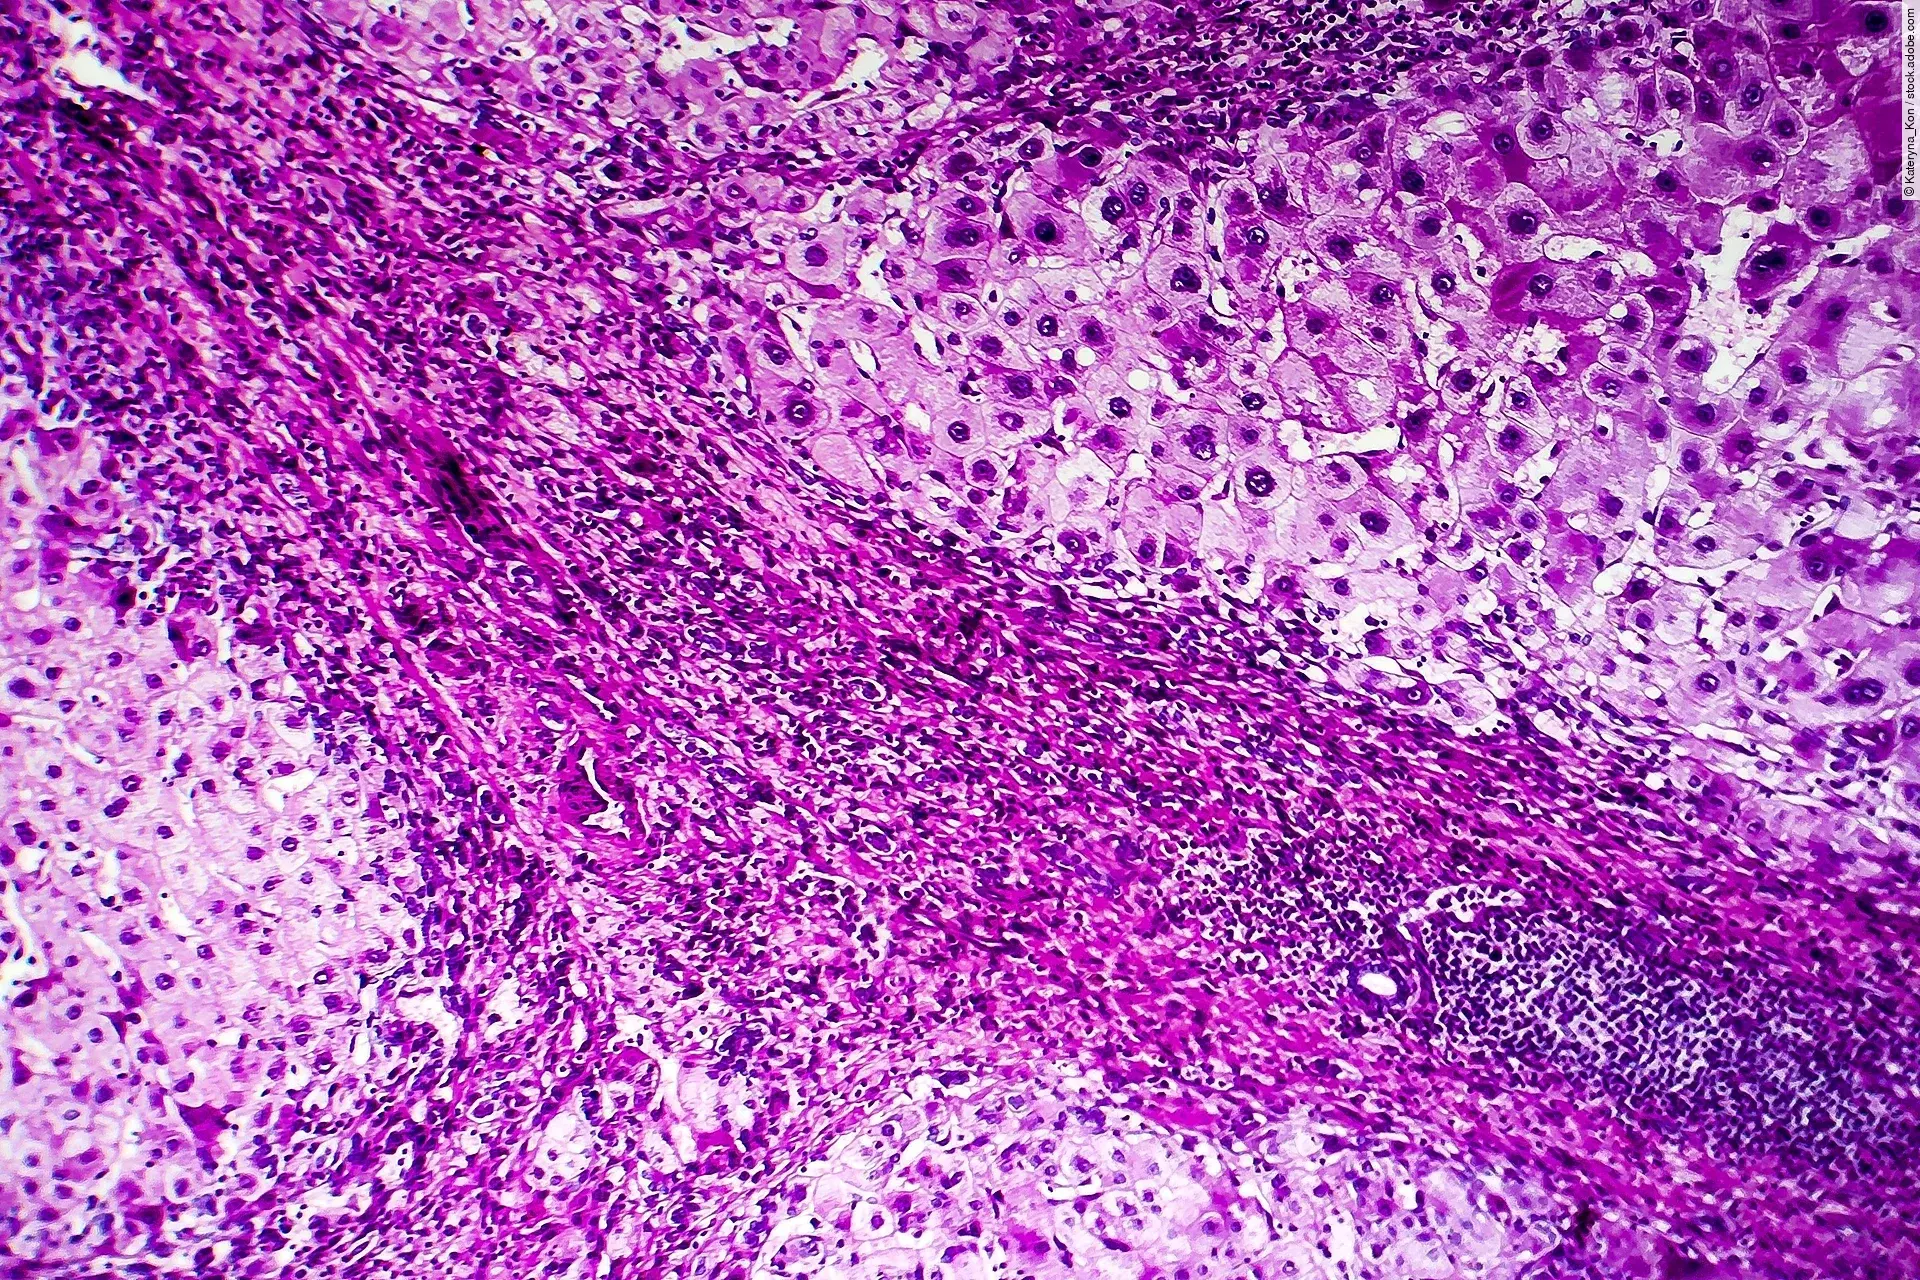

Da die Bildanalyse mittels KI bei der Auswertung histologischer Bilder immer bedeutsamer wird, haben Forschende nun eine Checkliste entwickelt, die höchste Qualität garantieren soll.